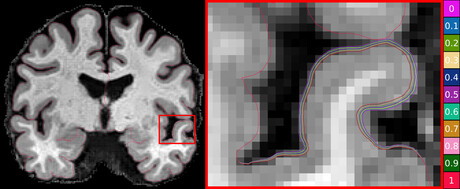

Assessing the onset and progression of Alzheimer’s using brain magnetic resonance imaging (MRI) has traditionally been challenging as changes in the thickness of the brain’s cortex are extremely small, often in the sub-millimetre range.

“Using the power of machine learning, we were able to produce a set of artificial MRI images of brains with predefined signs of neurodegeneration in the cortex region, the outer layer of the brain most affected by Alzheimer’s.

This new technique allows researchers to set the amount and location of brain degeneration they want to compare against so they can get a clear picture of what method of cortical thickness quantification performs the best.

The technique can test the sensitivity of methods to a miniscule level. It can determine whether a method can detect changes in thickness of just 0.01 millimetres.